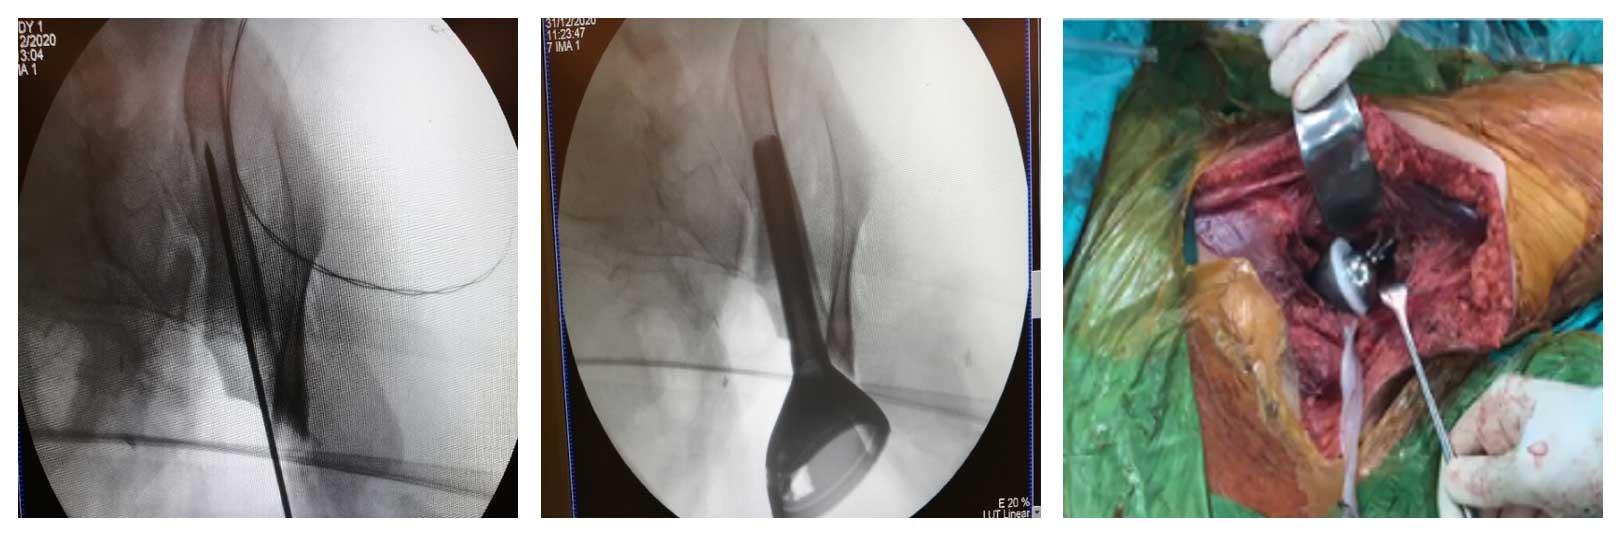

Ameliyat Esnası: Çıkarılan tümör dokusunun klinik ve skopi görüntüsü.

Ameliyat Esnası: Çıkarılan rezeksiyon dokusu ve protez uygulanımı görülmekte.